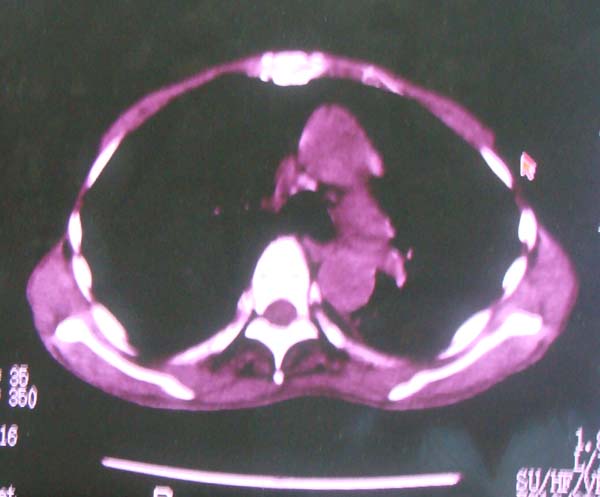

以下是引用zhangzhongshou在2008-2-15 22:25:00的发言:[br]片子照得不清,基本考虑1、细支气管肺泡癌2、亚急性血行播散型肺结核。请结合临床。片子细节显示不清,无法提供进一步意见。

以下是引用杀毒软件在2008-2-15 22:34:00的发言:[br]小叶中心性肺气肿。两肺弥漫性病变,肺泡微石病,过敏性肺炎,尘肺2期,特发性肺纤维化都有可能。[br]不象肺泡癌。